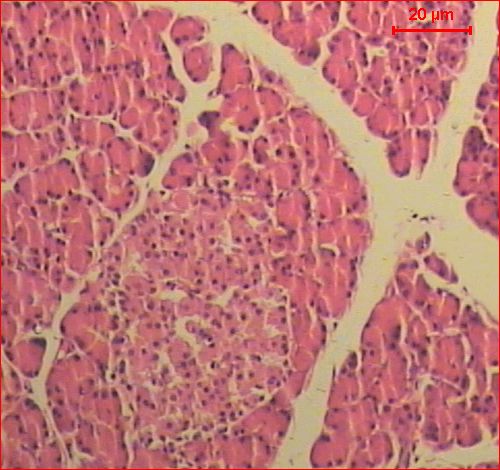

Sections of the control pancreas of rats showed the exocrine component of the pancreas that consisted of closely packed acini. The interlobular duct, surrounded with the supporting tissue. The endocrine tissue of the pancreas, islets of Langerhans, scattered throughout the exocrine tissue (fig. 2─A). Microscopic investigation of sections of pancreas of rats treated with 100 mg/kg b.w. of ethyl acetate or methanol extracts of Conyza dioscoridis for 21 days showed acinar cells and islets that were seen to be normal. The islets were present with volume and the numbers of pancreatic β-cell appeared more or less as control one (fig. 2─B, C).

The histopathological examination of pancreatic tissues revealed a decrease in pancreatic islet number and size, atrophy, and connective tissue invasion in the parenchyma of the pancreas islet was detected. On the other hand, a reduction in pancreatic β-cell numbers compared to the control group (fig. 2─D).

On treatment with 100 mg/kg b.w. doses of ethyl acetate extract of Conyza dioscoridis showed dramatic decrease in all abnormal histological changes as compared to the diabetic group (fig. 2─E). Significantly, lesser histological changes occurred in the methanol extract of Conyza dioscoridis treated group (fig. 2─F).

Fig. 2: Sections of the pancreas of A) control rat shows the exocrine component of the pancreas that consisted of closely packed acini. The interlobular duct, surrounded with the supporting tissue. The endocrine tissue of the pancreas, islets of Langerhans, scattered throughout the exocrine tissue, B, C) rats treated with ethyl acetate and methanol extracts of Conyza dioscoridis show the normal structure of the exocrine and endocrine pancreas, D) diabetic rat showed the acinar cells around the islets though seem to be in normal proportion does not look classical. A decrease in pancreatic islet number and size, atrophy, and connective tissue invasion in the parenchyma of pancreas islet was detected, E) diabetic rats treated with ethyl acetate extract of Conyza dioscoridis shows acinar cells and islets that were seen more or less like normal, and F) diabetic rats treated with methanol extract of Conyza dioscoridis shows lesser histological changes (H&E, Scale bar: 20 µm)